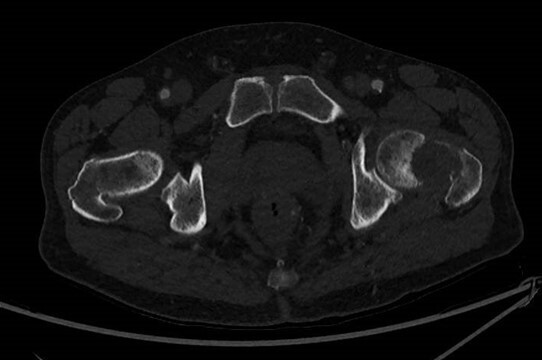

Vous n’observez pas de signe de lutte respiratoire, la dyspnée est silencieuse. L’auscultation pulmonaire retrouve une diminution du murmure vésiculaire à droite, accompagnée de sibilants localisés à mi-hauteur, la percussion révèle une matité. Les bruits du cœur sont réguliers, sans souffle. Il n’y a pas d’œdème des membres inférieurs, les mollets sont souples et indolores. Le reste de l’examen clinique est sans particularité.